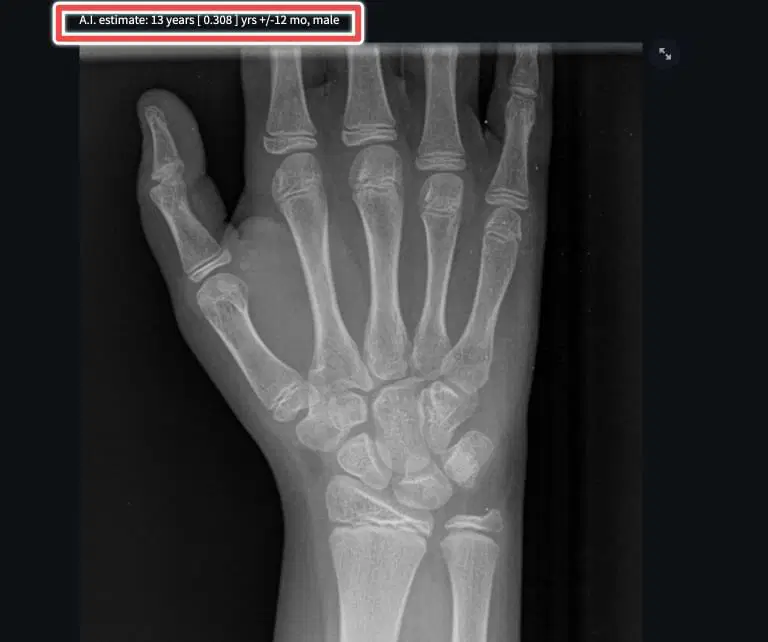

Example using Stanford tool

- Stanford Radiology Hand Bone Age AI – Automated

- FreeBoneAge.com – Automated

- 16bit.AI Bone Age Calculator – Paid